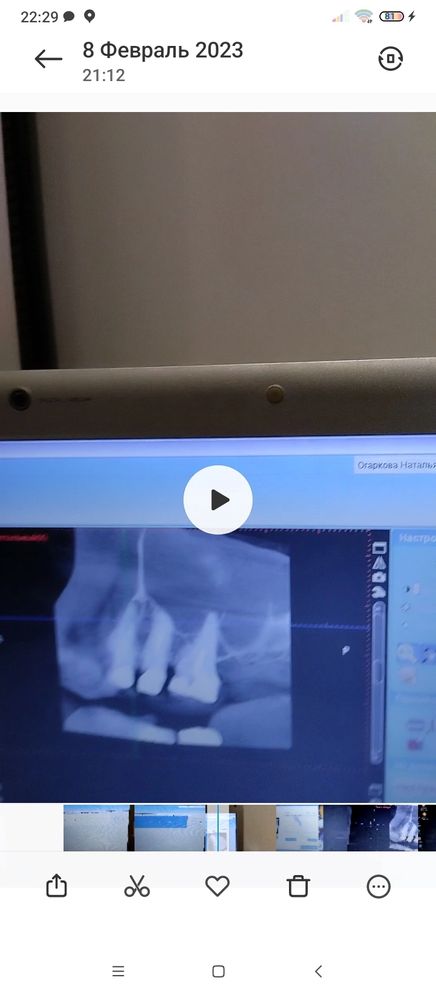

Доброго времени. После простуды начало закладывать нос, потом возникло воспаление щеки и дёсен, внешне не очень видно. при любом движении от зубов отдаётся в голову. Была температура 37,5,голова который день ватная. Есть подозрение на гайморит, но лор по телефону сказал что нужно сначала лечить зубы, потом гайморит. Сделала снимок, к зубному лечить попаду на приём только 15 го числа. Помогите расшифровать фото, тк врач к которому записалась и тот что первым смотрел снимок сказали совершенно разные вещи, один прописал антибиотик и лечение каналов одного зуба, а другой сказал что все не так плохо и назначил лечение другого зуба. И теперь я в ступоре кому верить и что делать, тк голова плывёт зубы при ходьбе ноют